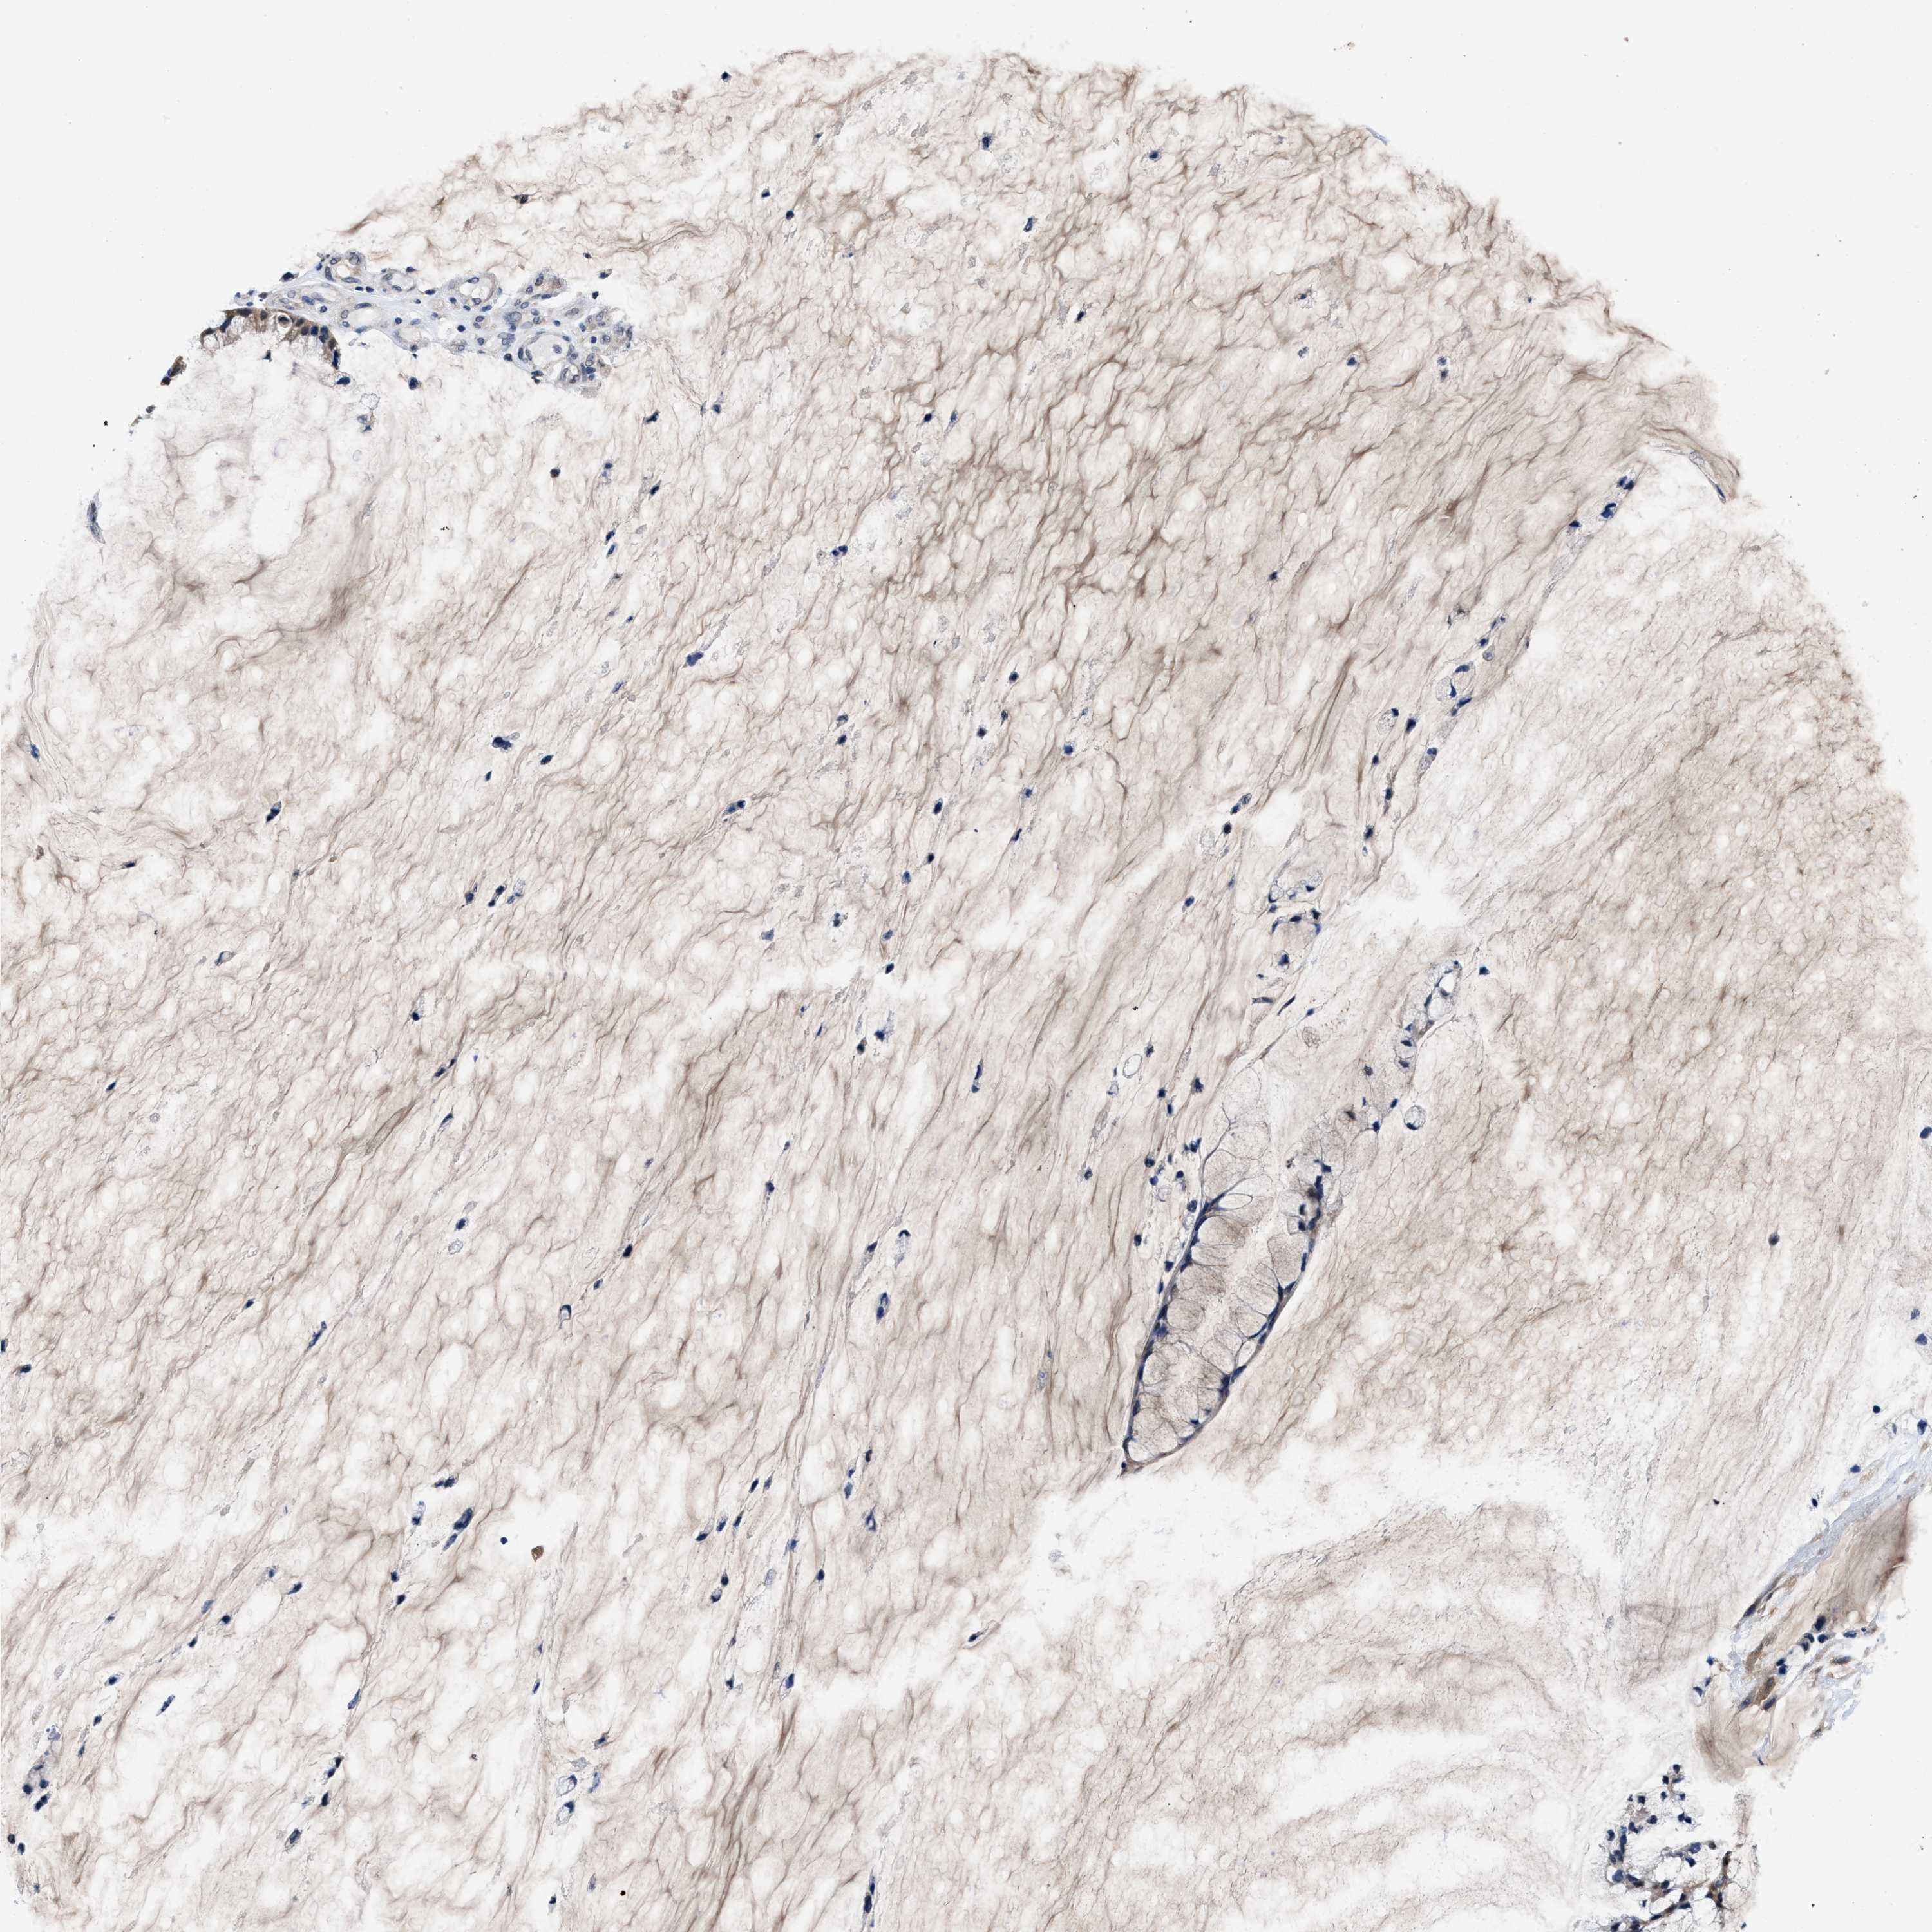

OVARIAN CANCER - Protein expressioni

A mouse-over function shows sample information and annotation data. Click on an image to view it in a full screen mode. Samples can be filtered based on level of antibody staining by selecting one or several of the following categories: high, medium, low and not detected. The assay and annotation is described here.

Note that samples used for immunohistochemistry by the Human Protein Atlas do not correspond to samples in the TCGA dataset.

Antibody stainingi

Antibody staining in the annotated cell types in the current human tissue is reported as not detected, low, medium, or high, based on conventional immunohistochemistry profiling in selected tissues. This score is based on the combination of the staining intensity and fraction of stained cells.

Each image is clickable and will lead to virtual microscopy that enables deeper exploration of all samples and also displays staining intensity scores, fraction scores and subcellular localization as well as patient and tissue information for each sample.

HPA022434

Cystadenocarcinoma, serous, NOS